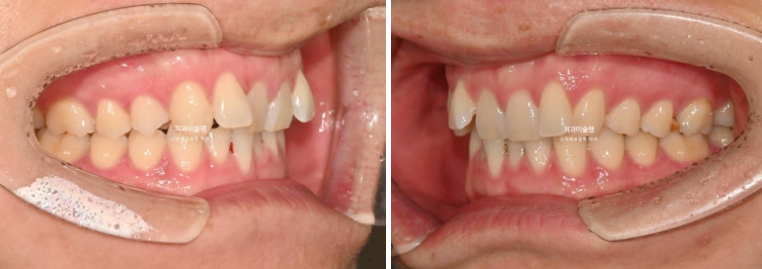

25.08

치료시작 4개월차 모습입니다.

윗니배열은 완벽하며

아랫니 배열이 조금 부족합니다.

약 2개월간 교정을 더 진행하여 10월, 드디어 장치를 뗍니다.